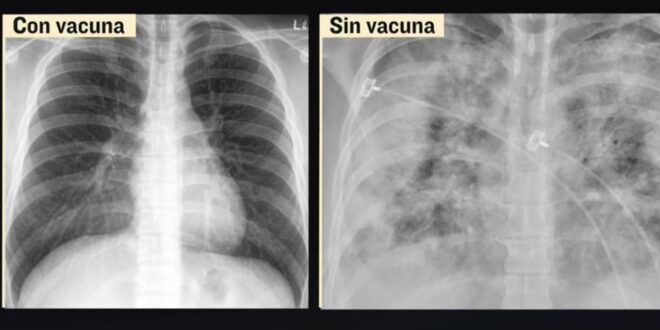

El daño que el coronavirus causó a los pulmones de un joven de 34 años, sano, pero sin haberse aplicado la vacuna fue grave.

“Esto que vemos aquí es el pulmón derecho, el pulmón izquierdo, vemos aquí la cinta cardiaca, esta burbuja que vemos aquí es el estómago, este lado corresponde al hígado y todo lo que vemos en color blanco -nosotros le llamamos imagen radiopacas- que es blanco, es justo donde están los focos neumónicos, el paciente prácticamente tiene una neumonía en su totalidad de ambos pulmones, estamos hablando quizá un 80, 90% de neumonía en ambos pulmones, ¿si no tuviera neumonía cómo se vería?Completamente negro”, dijo el radiólogo Jorge Albarrán.

El jefe del Departamento de Enfermedades Infecciosas de la Universidad de Maryland confirma, en este comparativo, que el daño en personas vacunadas, generalmente será más leve.